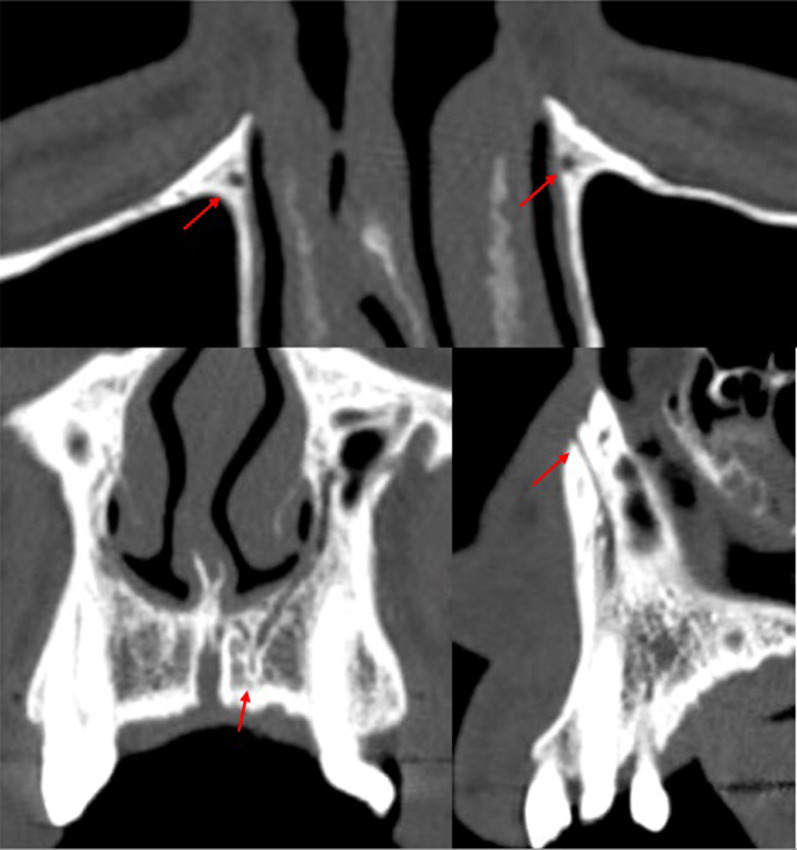

Fig. 7.

CS branches at different locations: Parallel to central incisor (A); Canine area bilaterally (B); Alveolar crest (C)